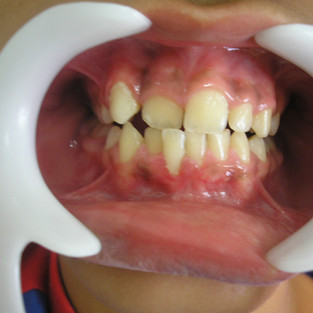

CORREÇÃO DE APINHAMENTO UTILIZANDO PLACA DE HAWLEY COM MOLA NO INCISIVO E POSTERIORMENTE APARELHO FIXO PARA FINALIZAÇÃO DO CASO;